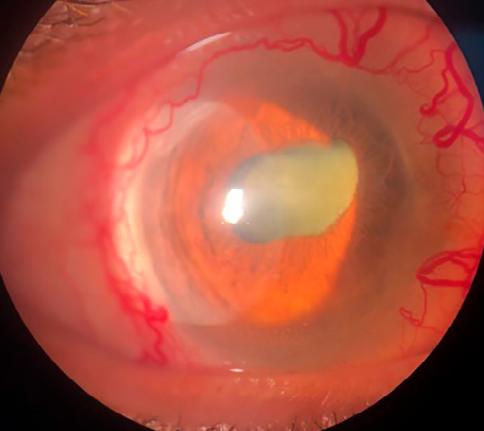

Se presenta en la guardia paciente femenina de 74 años de edad con cefalea, ojo rojo y disminución de la agudeza visual (AV) en ambos ojos, con predominio de ojo derecho (OD).

BMC OD: epiescleritis, limbitis, lesión nodular con adelgazamiento escleral nasal superior, catarata nuclear 3+ córnea clara sin Tyndal.

BMC OI: córnea clara, pupila corica reactiva leve hiperemia subconjuntival con dilatación venosa inferior catarata nuclear 2+.

PIO OD: 12 mmhg

PIO OI: 14mmHg

FONDO DE OJOS: aparenta retina aplicada con dificultad por opacidad de medios en ambos ojos.

Considerando el cuadro clínico de la paciente, sus antecedentes patológicos y los resultados del examen oftalmológico completo realizado, se confirma la sospecha de escleritis nodular y se indica iniciar prontamente tratamiento con meprednisona vía oral 20 mg día asociado a acetato de prednisolona al 1 % cada 2 horas, Gatifloxacina cada 3 horas e Hidroximetilcelulosa (HMC).

Sin embargo, la paciente no concurre al control, se presenta pasados 20 días de la consulta inicial sin realizar el tratamiento indicado y con dolor ocular que no sede con AINES y franca disminución de AV.

Se realiza un nuevo examen oftalmológico que arroja:

AV OD: PLSP (mala proyección luminosa))

AV OI: 1/10 SC NMCE

BMC OD: Inyección cilio-conjuntival, placa de necrosis con adelgazamiento escleral en región nasal superior, catarata total, seclusión pupilar, PQ finos y abundantes células en cámara anterior.

BMC OI: Adelgazamiento escleral nasal superior, dilatación venosa, sinequias posteriores y catarata nuclear 2+.

PIO OD: 9 mmHg

PIO OI: 12 mmHg

Se detecta evolución a escleritis necrotizante aguda y se decide internación para realizar pulsoterapia con metilprednisolona 1 g/día endovenoso por 5 días.